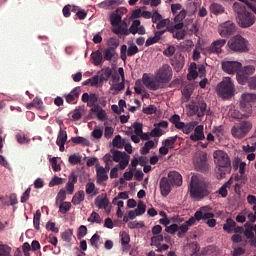

Setup. We evaluate all models on the Camelyon16 Whole Slide Image cancer detection dataset (Bejnordi et al., 2017). Each instance consists of a high resolution image of tissue from a medical scan which is pre-processed into patches of RGB pixels. After pre-processing, the average number of patches in a single set is over 9,300 (7.3GB), making each input roughly equivalent to processing 1% of ImageNet1k (Deng et al., 2009). The largest input in the training set contains 32,382 patches (25.4 GB). We utilize a ResNet18 (He et al., 2016) which is pretrained on Camelyon16 (Li et al., 2021) via SimCLR (Chen et al., 2020) as a backbone feature extractor whose weights can be downloaded from this repository111https://github.com/binli123/dsmil-wsi. Our goal is to first pretrain MBC set encoders on the extracted features, and then use the unbiased estimation of the full set gradient to fine-tune the feature extractor on the full input sets. We evaluate the performance of UMBC against non-MBC MIL baselines: DS-MIL (Li et al., 2021) and AB-MIL (Ilse et al., 2018), as well as MBC baselines: DeepSets and SSE.

The Camelyon16 Whole Slide Image dataset consists of 270 training instances and 129 validation instances. The dataset was created for a competition, and therefore the test set is hidden. We therefore follow the example set by previous works (Li et al., 2021) and report performance achieved on the validation set. For preprocessing, we consider the slide magnification setting, and use OTSU’s thresholding method to detect regions containing tissue within the WSI. We then split the activated regions into non overlapping patches of size . An example of single input patches can be seen in Figure 12. The largest input set contains image patches which are each . All patch extraction code can be found in the supplementary file. Table 14 contains statistics related to the numbers of patches per input for the training and the test set as well as the distribution of positive and negative labels.